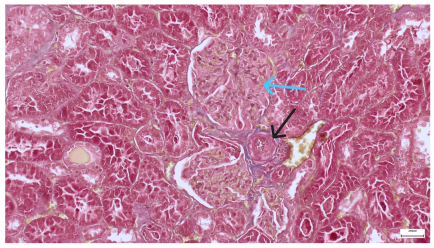

Table 4 below presents histological proof for renal damage in the G-IV group suffering from a dual metabolic impairment, albeit treated with statin.

Table 4.

Histological proof for renal damage in the diabetic-and-obese statin-treated group G-IV.

The histological extent of lesions suggests a definite inflammatory process in the renal matrix and glomeruli, but the extent of the disruptive process as resulting from an average nephron pool loss is limited. This is consistent with the limited duration of our experiment, with definite development of chronic kidney disease taking sometimes as long as 24 weeks. However, expecting this limited extent of damage, we chose a relatively short—proportionate—duration of statin treatment. Our results demonstrate a statistically significant higher retention of creatinine and urea in plasma—a reflection of the respective reduction in renal function—in every single experimental group (G-II to G-IV) in comparison to the control group G-I. The diabetic group G-III demonstrates the highest values for both creatinine and urea across the whole experiment population. The plasma concentrations of retention byproducts in both G-II and G-III are statistically significantly higher compared to the control G-I, indicating that each condition independently leads to important impairment in kidney function. The assumption of concurring actions in a model exhibiting obesity and diabetes simultaneously should translate into outcomes—renal and inflammatory—with values skewed from normality, the dimension of departure from the normal range at least as big as in any of the models exhibiting an individual condition.